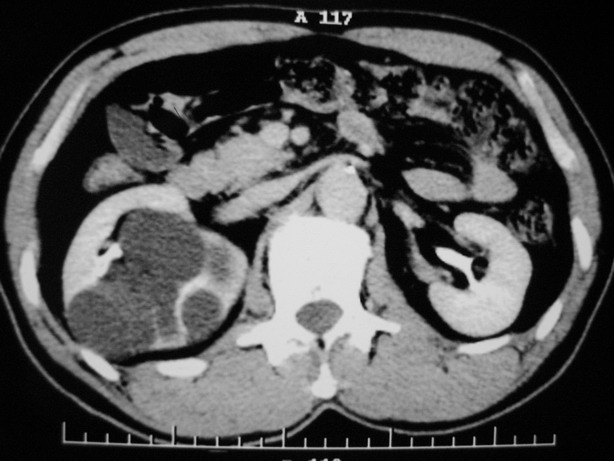

肾盂旁多囊性占位,有实性成分,增强有轻度强化,收集期病变内无造影剂显影。诊断肾盂旁囊肿,有实性成分无法解释,查书后诊断为:多房性囊性肾瘤!!不知大家同意否?????????对本病知道不多,望大家不吝赐教!!

不除外囊性肾癌

支持囊性肾癌。

右肾多发囊性低密度影,囊内有增强的隔及实性组织,考虑囊性肾癌。

考虑囊性肾癌